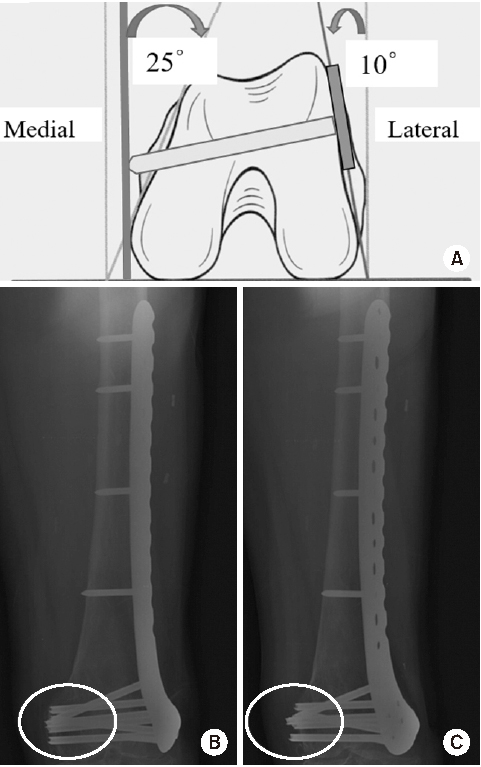

Fig. 5

(A) Schematic diagram showing the axial shape of the distal femur and the appropriate length of distal locking screw. (B) Anteroposterior (A–P) and lateral photos showing the appropriate position of the lateral anatomical locking plate in the distal femur model. (C) A–P and lateral radiographs showing the appropriate position of the locking plate fixed in a distal femur fracture of a 72-year-old female patient.